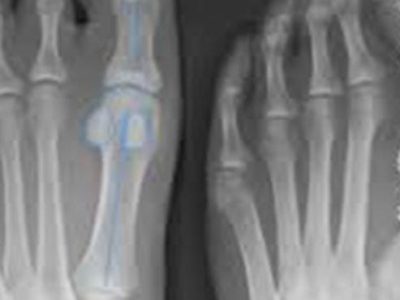

The short answer from an orthopaedic surgeon Q: I have bunions, and they’re becoming bothersome to me. Should I think about having surgery? How do I know when it’s time to consider a procedure? A: Bunions are common, annoying and painful. Just…